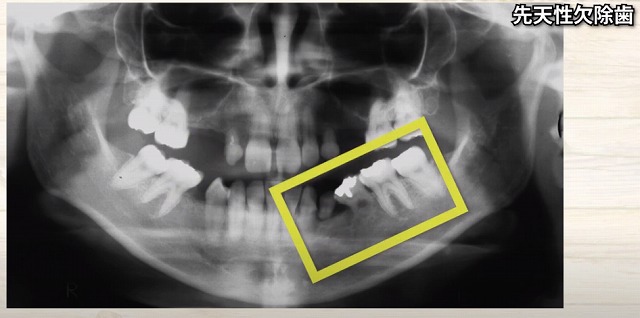

こちらは

子供の歯があって

その下に大人の歯が控えている写真です。

反対側は

子供の歯はありますが

大人の歯が見当たりません

つまり

もともと

大人の歯が

骨の中に控えていない

生えてこない

ということです。

この方は

子供の歯の大人の歯に囲まれて

見えなくなっています。

何が

起こってしまったのでしょうか?

この方は

こんなにも歯が足りません。

歯の根っこの長さに注目すると

短い・短い子供の歯です。

後ろは大人の歯が生えてきました。

後ろから手前に大人の歯が倒れてくると

簡単に子供の歯は

埋まっている根っこが短いですから

簡単に押し倒されてしまいます

もともと大人の歯が生えていないから